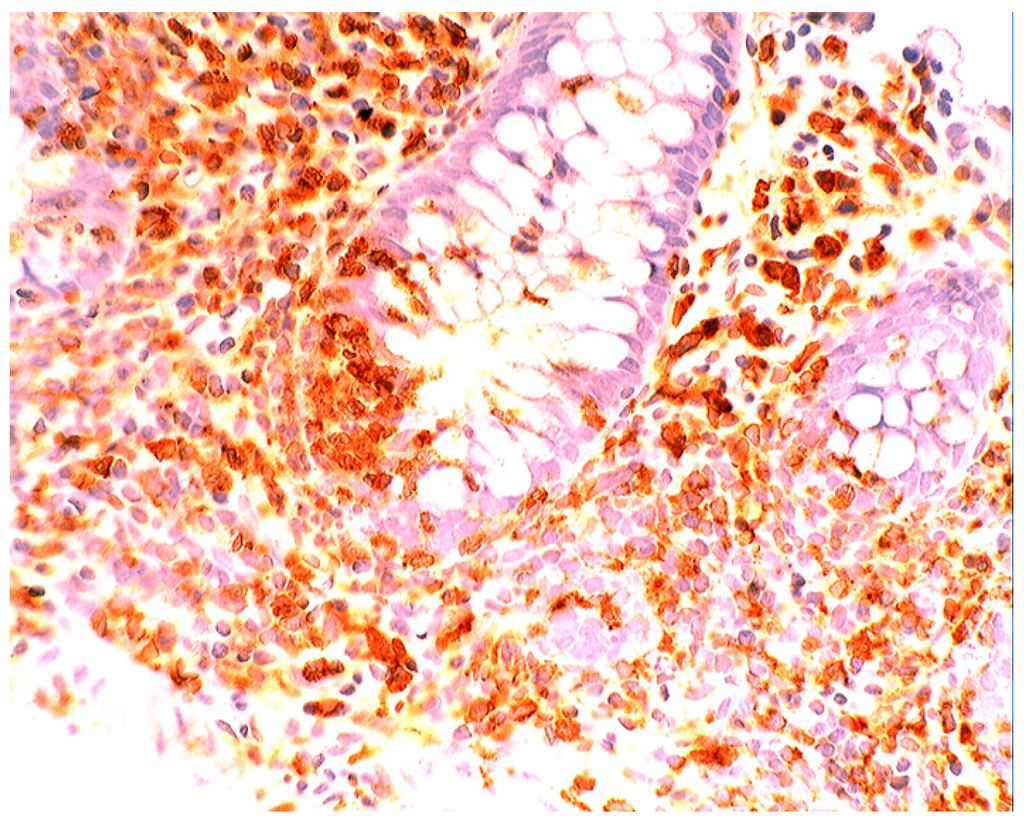

In collagenous colitis lysozyme is up-regulated in the colonic crypts and in metaplastic Paneth cells [9] (Figure 11). In lymphocytic colitis, lysozyme is up-regulated in macrophages underlying the surface epithelium of the lamina propria [9] (Figure 12), as well as in the lower part of the crypts (Figure 13).

Figure 12.

Lymphocytic colitis showing marked lysozyme expression, in macrophages in the lamina propria juxtaposing the superficial epithelium (lysozyme immunostain, ×40).